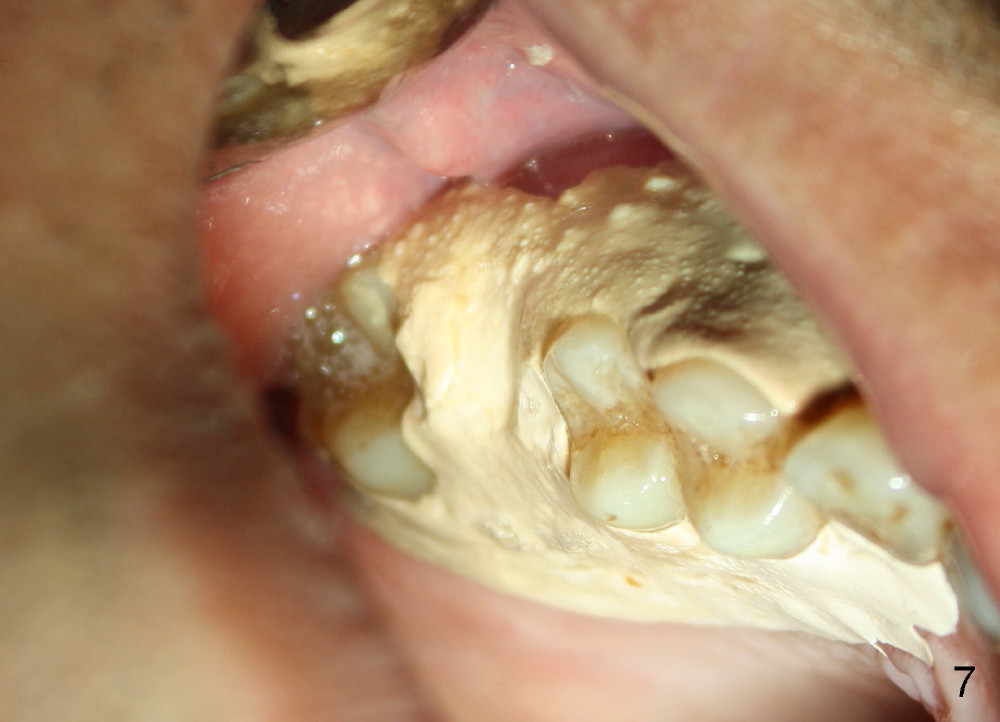

The tooth #3 has a crack line (Fig.1 ^). The septum (Fig.2 S) looks like an inverted pyramid (Fig.3), coronal part being pointed, whereas the apical broad. The shape of the septum is not so favorable to placement of tapered implant. Osteotomy starts with 1.5 mm pilot drill in the middle of the septum, followed by round tapered osteotomes 2 and 3 mm. The osteotomy begins to deviate into the mesiobuccal socket. The same osteotomes are used to re-direct the osteotomy palatally, followed by tapered drills, trying to move osteotomy palatally. A 4.5x17 mm tap is inserted with stability (Fig.4). Following using 5x17 mm tap at the depth of 12 mm, a 5.3x12 mm bone-level implant is placed ~ 1.5 mm below the crest, 1.5 mm above the septum (Fig.5). Demineralized cortical human allograft is placed in the remaining sockets and around the most coronal aspect of the implant (with a small piece of gauze placed in the implant well). After removal of the gauze, a piece of collagen membrane is pierced and carried by a 8.2x4/3 mm healing abutment and fixed in place (Fig.6 M). The periphery of the membrane is tucked underneath the gingiva. The wound is covered by perio dressing. The patient returns to clinic for follow up 8 days postop. There is no discomfort. In order to protect the collagen membrane (Fig.6), the perio dressing is intentionally not removed (Fig.7). Two weeks postop, the patient remains asymptomatic. After perio dressing removal, the membrane appears to have been resorbed (Fig.8 as compared to Fig.6). The bone graft (B), although exposed, remains in place and condensed, surrounded by healing healthy gingiva (*). The patient returns 2.5 months postop. The implant appears to osteointegrate (Fig.9, as compared to Fig.5). The buccal (Fig.10) and palatal (Fig.11) gingiva adapts to the healing abutment. When the healing abutment is removed for restoration 3 months postop, the gingiva looks healthy (Fig.12). A cemented abutment (5.8x4(2) mm) is placed; a crown is fabricated (Fig.13). The patient returns for recall 5 months post cementation. He reports food impaction distal to the crown. The gap mesial to the implant has closed (Fig.14).